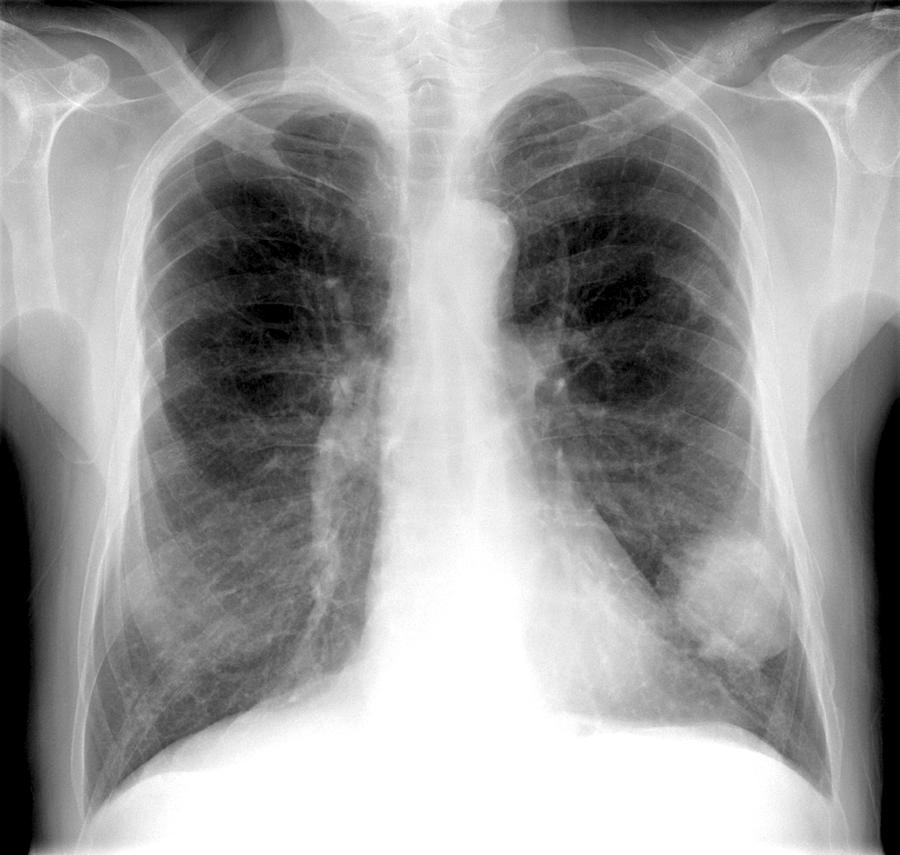

Lung Cancer Screening X Ray

Experience the clarity of Lung Cancer Screening X Ray with our curated collection of comprehensive galleries of images. featuring understated examples of photography, images, and pictures. designed to emphasize clarity and focus. Discover high-resolution Lung Cancer Screening X Ray images optimized for various applications. Suitable for various applications including web design, social media, personal projects, and digital content creation All Lung Cancer Screening X Ray images are available in high resolution with professional-grade quality, optimized for both digital and print applications, and include comprehensive metadata for easy organization and usage. Our Lung Cancer Screening X Ray gallery offers diverse visual resources to bring your ideas to life. Comprehensive tagging systems facilitate quick discovery of relevant Lung Cancer Screening X Ray content. Multiple resolution options ensure optimal performance across different platforms and applications. Time-saving browsing features help users locate ideal Lung Cancer Screening X Ray images quickly. The Lung Cancer Screening X Ray archive serves professionals, educators, and creatives across diverse industries. Instant download capabilities enable immediate access to chosen Lung Cancer Screening X Ray images. Whether for commercial projects or personal use, our Lung Cancer Screening X Ray collection delivers consistent excellence. Professional licensing options accommodate both commercial and educational usage requirements.